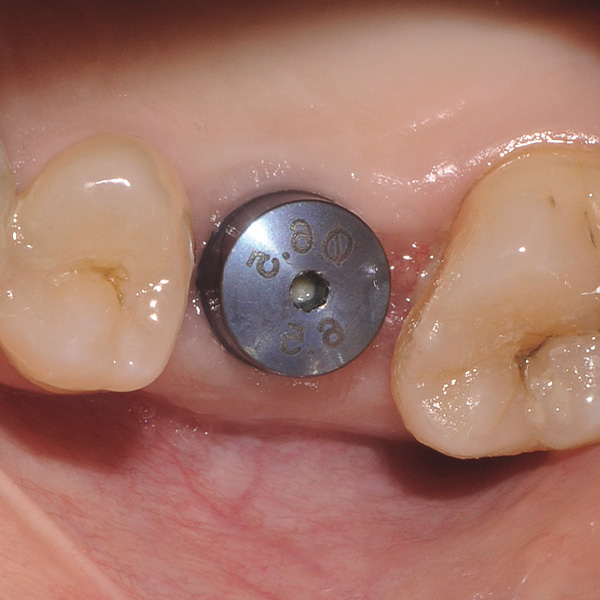

Reconstrucción de corona implantosoportada de cerámica híbrida VITA ENAMIC multiColor

Sobre todo las restauraciones sobre implantes están sometidas a elevadas solicitaciones. Tras la extracción y el implante, al paciente le falta el tejido fibroso elástico del lecho dental natural. En consecuencia, no se absorben las fuerzas oclusales, sino que se transmiten directamente a la restauración, al implante, al hueso y a los dientes antagonistas. La cerámica híbrida VITA ENAMIC incorpora una matriz dual de cerámica (86 % del peso) y polímero (14 % del peso). Esto le otorga una elasticidad similar a la de la dentina y la capacidad de absorber fuerzas oclusales. Gracias a su elevada dimensión vertical, la pieza en bruto policroma VITA ENAMIC multiColor en la geometría EMC-16 posibilita, incluso en caso de hueso atrofiado, la confección de coronas sobre pilar monolíticas de una pieza. El doctor y catedrático Alexander Hassel muestra en el siguiente artículo cómo ha tratado a una paciente empleando este método de restauración.